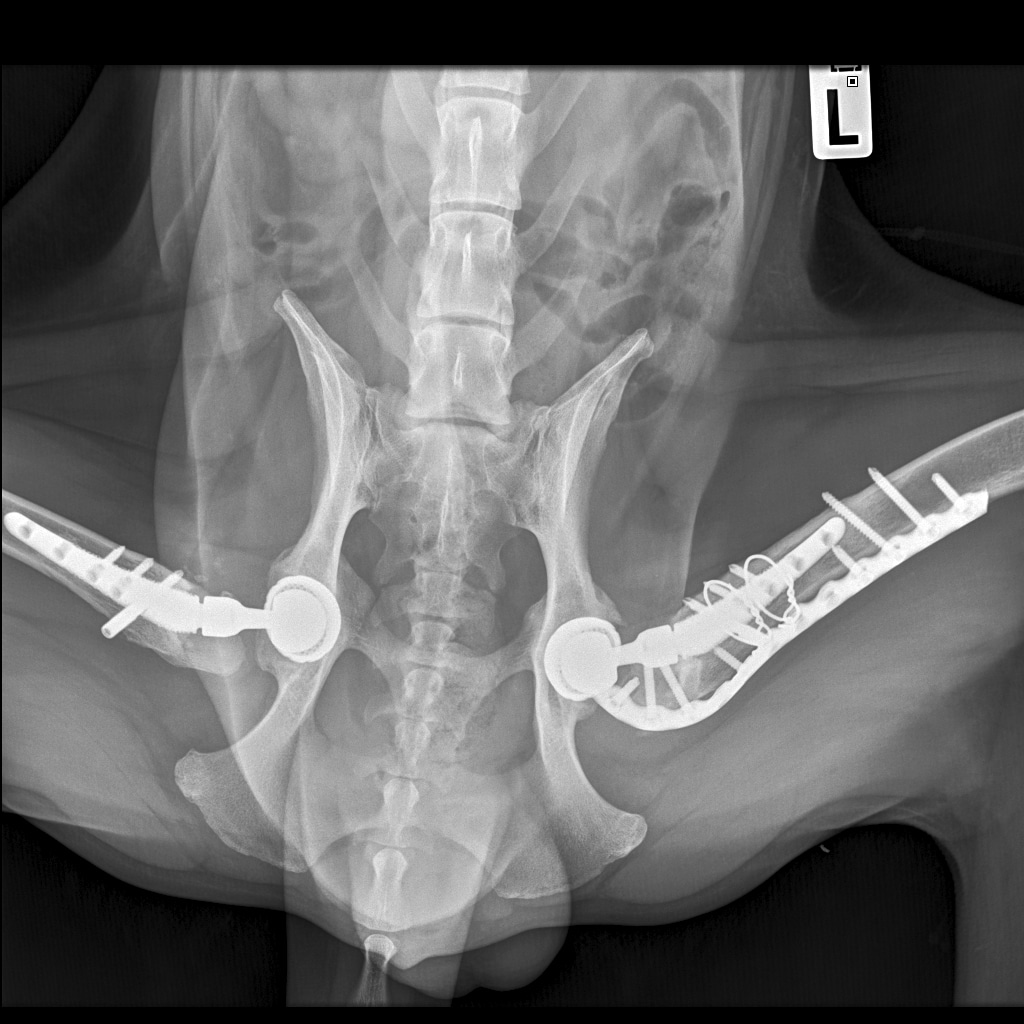

Вчера резко захромал, встал на 3 ноги и понос.

По рентгену чисто

Здравствуйте, с. Бруно по плану перед началом курса Амикацина

- Контроль крови БХ( Мочевина, креатинин, фосфор)

- Анализ мочи соотношение ГГТ\Креатинин

При отс. противопоказаний:

- Амикацин 1 гр(1000мг) Ампула - развести в 5 мл натрия хлорида 0.9% набрать 3 мл внутримышечно 1 раз в сутки до отмены Васильевой Е.А. ( Минимальный курс 6 недель)

После начала курса Амикацина необходим контроль

- Анализ мочи ГГТ//Креатинин 1 раз в 3 дня.

По плану через 3 недели записаться к Васильевой Евгении Александровне на забор материала на цитологию и бактериологический посев повторно в динамике.